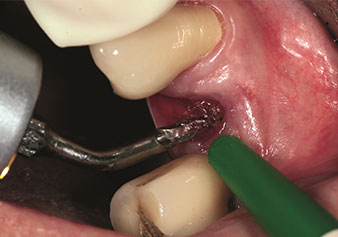

W&H also offers the perfect solution for the internal sinus lift.

Following preparation of the maxillary sinuses with the corresponding instrument set (Fig. 3), the new Z35P instrument (Fig. 4) is used to lift the membrane hydrodynamically. The same instrument set can also be used for piezosurgical preparation of the implant bed in increasing diameters (Figures 3 and 4 included with the kind permission of Dr Mario Kirste, Frankfurt/Oder).

Preparation of implant bed with I4P instrument

Fig. 3: Preparation of implant bed with I4P instrument. Photo: © Dr Mario Kirste (Frankfurt / Oder)